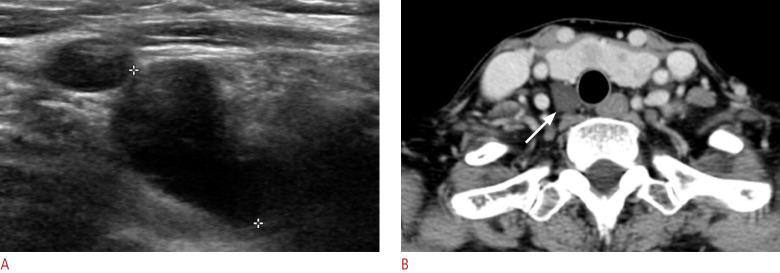

The parathyroid glands play a key role in maintaining calcium-phosphate homeostasis by secreting parathyroid hormone (PTH). Hyperparathyroidism, characterized by the inappropriate overproduction of PTH, is classified as primary, secondary, or tertiary according to its pathophysiology. Although diagnosis is principally biochemical, imaging is essential for accurately localizing hyperfunctioning glands. Precise localization allows for focused minimally invasive surgery, reduces the risk of persistent or recurrent disease, and avoids unnecessary bilateral neck exploration. Current techniques include high-resolution ultrasonography, 99mTc-sestamibi scintigraphy with single-photon emission computed tomography/computed tomography (CT), four-dimensional CT, magnetic resonance imaging, and positron emission tomography/CT with tracers such as 18F-fluorocholine. Parathyroidectomy remains the mainstay of treatment; however, recent advances in thermal ablation have expanded treatment options for patients unsuitable for surgery.

甲状旁腺通过分泌甲状旁腺激素(PTH)在维持钙磷稳态中起关键作用。甲状旁腺功能亢进症的特征是PTH分泌过多,根据其病理生理学可分为原发性、继发性或三发性。虽然诊断主要依靠生化检查,但影像学检查对于准确定位功能亢进的腺体至关重要。精确的定位有助于进行有针对性的微创手术,降低持续性或复发性疾病的风险,并避免不必要的双侧颈部探查。目前的技术包括高分辨率超声检查、99mTc-甲氧基异丁基异腈闪烁显像联合单光子发射计算机断层扫描/计算机断层扫描(CT)、四维CT、磁共振成像以及使用18F-氟胆碱等示踪剂的正电子发射断层扫描/CT。甲状旁腺切除术仍然是主要的治疗方法;然而,热消融技术的最新进展为不适合手术的患者扩展了治疗选择。